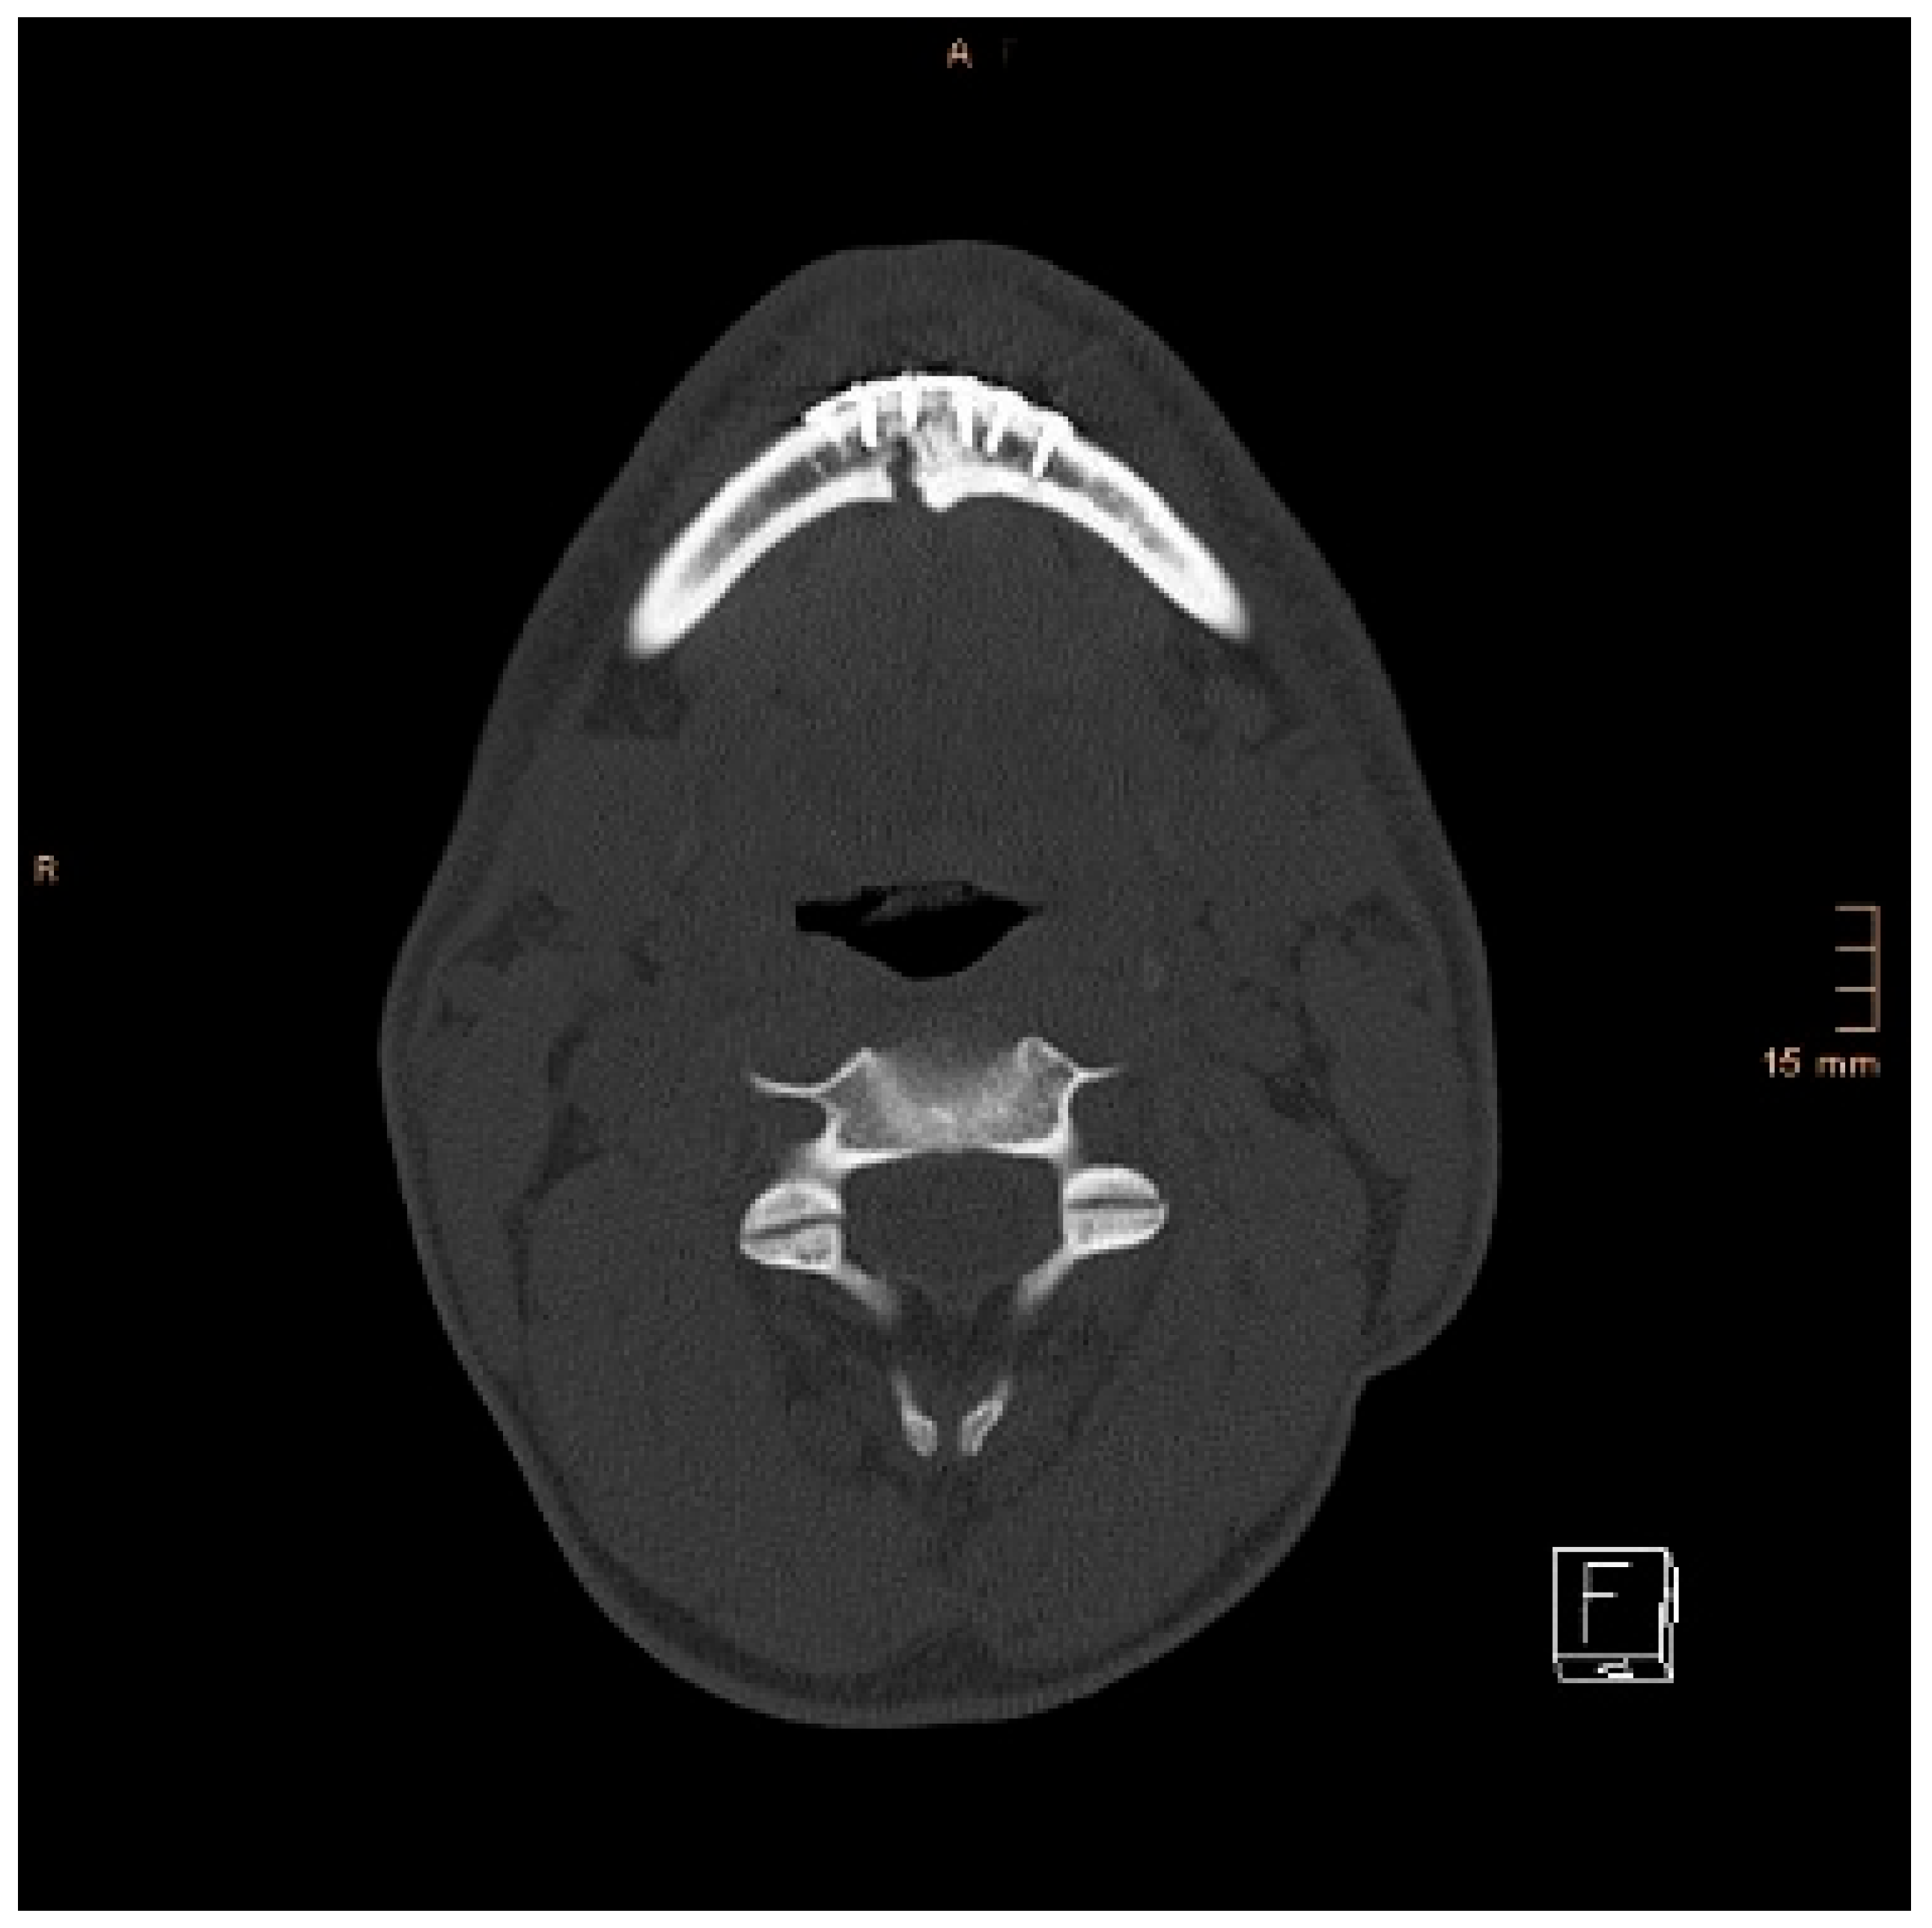

Figure 8 and Figure 9 below show another patient with a non-satisfactory reduction in the condylar neck fracture on the left-hand side due to a lingual gap present at a body fracture (Figure 8 and Figure 9).

Figure 8. Coronal CT scan showing a condylar neck angulation on the left side after ORIF. An anatomical reduction could not be achieved.

Figure 9. Axial CT scan showing the same patient as in Figure 8. A lingual gap is present after ORIF of the mandibular body fracture, contributing to the inability to reduce the condylar fracture correctly.